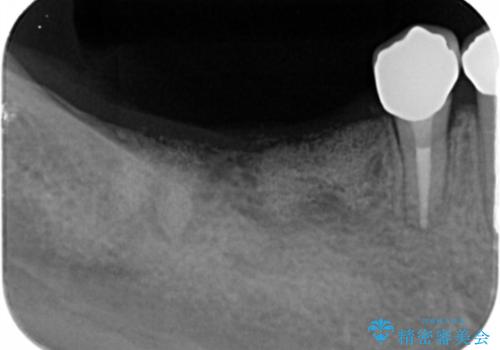

X線写真検査より、クラウンや銀歯の下で歯に大きな虫歯が発生し、抜歯を余儀なくされる状況でした。

虫歯に伴い歯槽骨の吸収も見られたので造骨後、インプラントを用いて咬合機能を回復します。